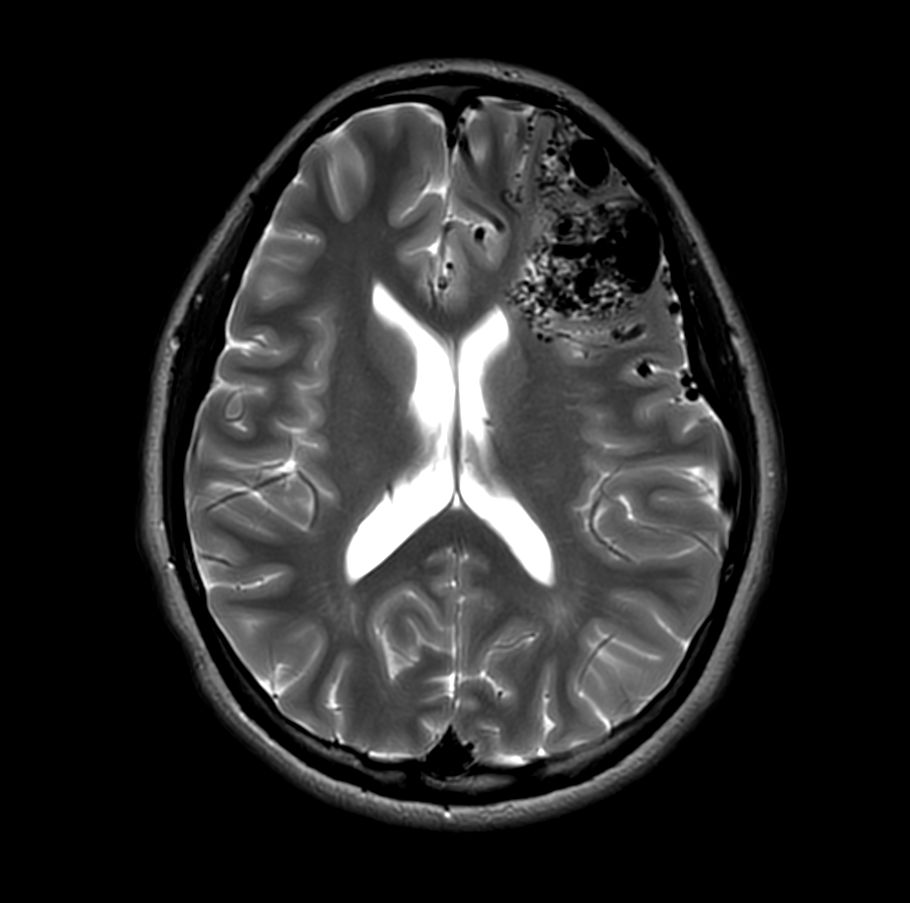

Axial T2w TSE MultiVane XD

-